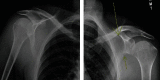

The violent nature of generalized tonic-clonic seizures puts individuals at risk of a large number of potential injuries. These can occur due both to the profound muscular contractions that accompany these episodes as well as falls and other traumatic events that occur due to the period of loss of consciousness that occurs during generalized seizures. While injuries such as soft tissue contusions, tongue biting, dental injuries, and facial lacerations resulting from falls from standing predominate, bony injuries are not uncommon. We present a case of bilateral scapular fractures that occurred in an otherwise healthy 32-year male who presented with shoulder and back pain and inability to perform any significant movement of his upper arms secondary to pain after experiencing an apparent first-time generalized tonic-clonic seizure. The presence of unilateral and bilateral scapular fractures, while uncommonly described, should be considered as an additional potential orthopedic injury that may occur secondary to a generalized tonic-clonic seizure. In the absence of observed significant forceful traumatic injury, this injury is unusual, and its presence noted in a patient experiencing sudden loss of consciousness should raise heightened concern of seizures as the potential etiology.